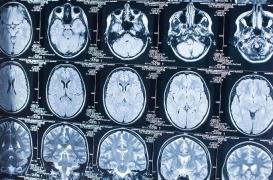

LES MALADIES

SYMPTÔMES